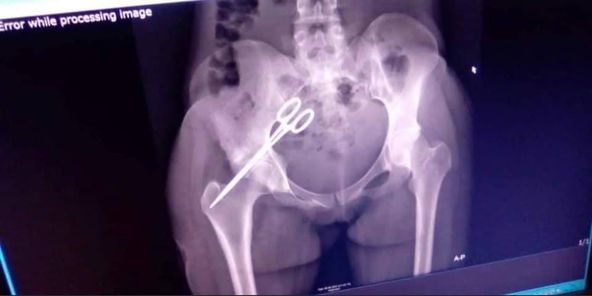

Scissors has been removed from the pelvic area of Sierra Leonean lady, Zainab Kamara, 7 years after Doctor’s negligence left her in that state.

Kamara who went for a Caesarian operation and lost the baby at Port Loko district was left with constant pains after a doctor that operated her forgot scissors inside her Stomach that later moved to her pelvic.

Sierraloaded learnt that She has been suffering with this pain for 7years and later an X-ray was done on her and the results shows Scissors is in a pelvic area according to sources doctors were scared to do the operation because they think itβs a risky one.

According to Hawanatu Konneh’s Blog, after 7 years the Scissors was removed by an Expert from another country at the Masanga Hospital Tonkolili District.